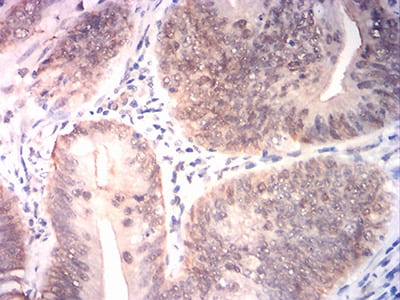

分类: 科研抗体货号: 31816别名: OF; BACH1; FANCJ应用: IHC,FCM反应种属: Human